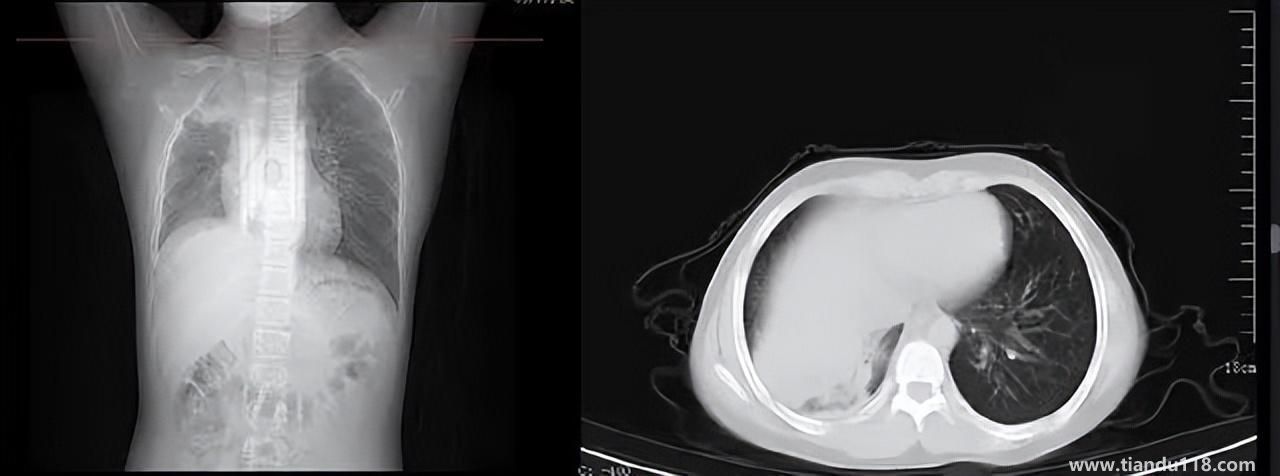

3個辦法可提前預(yù)警白肺(咋預(yù)防“白肺”) 3個辦法可提前預(yù)警白肺(咋預(yù)防“白肺”)家里有老人,擔(dān)心出現(xiàn)“大白肺”、“沉默型缺氧”等情況,具體如何應(yīng)對,提前預(yù)警?近日,大象新聞接到諸多咨詢。針對這些問題,大象新聞記者做了多方采訪。什么是白肺?對... 小編 2022-12-28 693

男孩咳嗽發(fā)熱在家硬扛成白肺(醫(yī)生表示以下幾種情況別硬“扛”) 男孩咳嗽發(fā)熱在家硬扛成白肺(醫(yī)生表示以下幾種情況別硬“扛”) 近日,一名12歲男孩咳嗽一周不就醫(yī),一側(cè)肺部“扛”成了“白肺”。“抱著僥幸心理一直在家硬‘扛’,沒想到‘扛’出這么重的病!”孩子家長悔不... 小編 2022-12-28 939

為何有人出現(xiàn)“白肺”?專家回應(yīng)和疫苗接種無關(guān) 為何有人出現(xiàn)“白肺”?專家回應(yīng)和疫苗接種無關(guān)國務(wù)院聯(lián)防聯(lián)控機制12月27日召開新聞發(fā)布會,針對有媒體提問稱,從近期公眾的反映情況看,有的新冠病毒感染者在就診過程中發(fā)現(xiàn)了肺炎或者是CT出現(xiàn)了“白肺”的現(xiàn)... 小編 2022-12-27 817

感染新冠會變白肺?醫(yī)生:有年輕病例 感染新冠會變白肺?醫(yī)生:有年輕病例感染新冠會變白肺嗎?對此,有專家表示,造成“白肺”情況有很多種,感染新冠只是一種可能。少量患者肺有滲液 ,咳嗽不會引發(fā)白肺,有年輕人病例。... 小編 2022-12-27 608